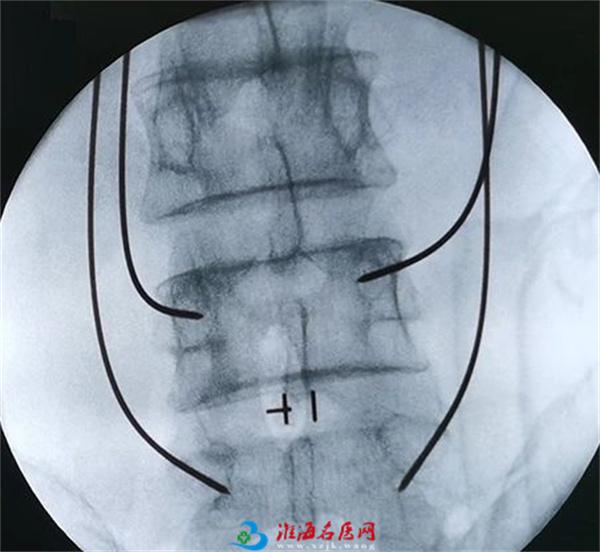

术中

这时候再结合骨科机器人,根据术前规划路径,自动调节进针角度、分析确定定位点,并智能自动寻找。在骨科机器人的帮助下,医生只需在置钉部位切开约2cm切口,这样不损伤其它椎关节,保障了神经安全,使手术更精准、更微创、患者更快康复。